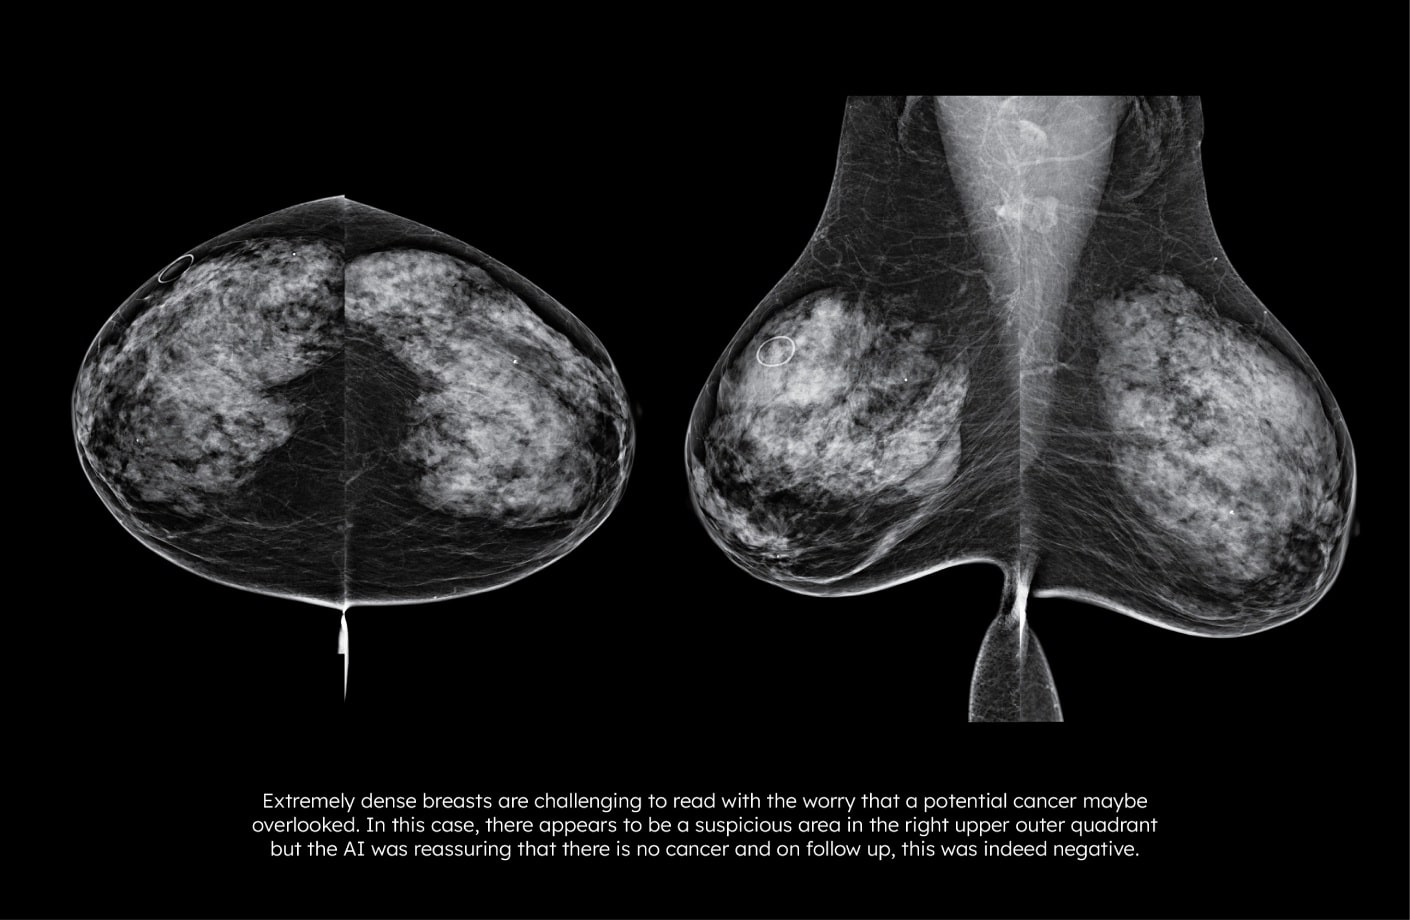

By improving specificity*, Lunit INSIGHT MMG reduces false positives and unnecessary callbacks. This supports more confident interpretation, lowers patient anxiety, and reduces follow-up burden on clinical teams.

*Kwon, Mr., Chang, Y., Ham, SY. et al. Screening mammography performance according to breast density: a comparison between radiologists versus standalone intelligence detection. Breast Cancer Res 26, 68 (2024).